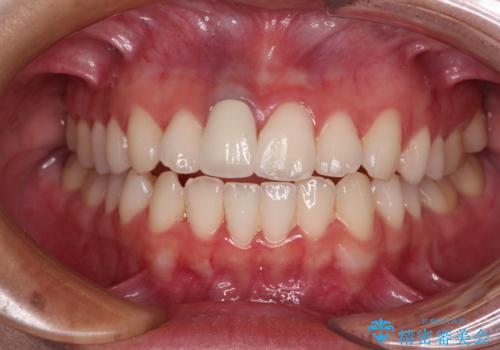

あっという間に気になっていた変色が解決し、早く治療を始めれば良かったとおっしゃっていました。

オーダーメイドタイプのクラウンを選択いただいたので、まるで天然の歯と見間違うほど自然に仕上がり、患者様には大変満足していただきました。